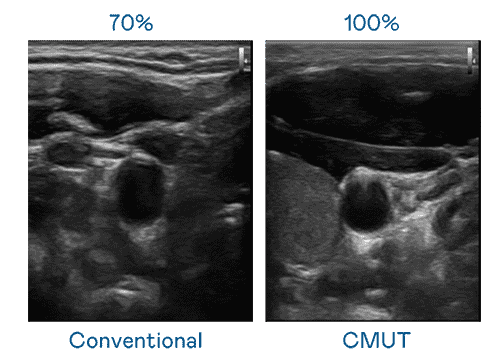

CMUT 技术是一种用电容式微机电元件来产生超音波讯号的技术。。。。与传统 PZT 压电式技术相比,,,CMUT 频宽增加 30%,,,更宽频的超音波讯号让影像解析度大幅提升,,,,是实现高影像品质医疗超音波扫描、、、、促进精准医疗发展的关键技术。。。

大频宽带来超清晰影像

超音波影像的解析度高低,,首先取决于探头能发出的讯号频宽。。。。2468BET CMUT 可提供高清晰的超音波讯号,,,,提供高频宽、、、高灵敏度、、、影像纹理细节更高的超音波影像,,,协助医护人员缩短影像判读时间及利用精准的医疗影像进行诊断。。。。